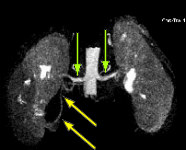

FINDINGS: The ultrasound (not shown) demonstrated dilated collecting system versus extrarenal pelvis on the right. Fig. 1 and Fig. 2 are nephrographic and delayed images through the kidneys. They demonstrate a large dilated right renal pelvis (red arrows) with urine-contrast level and a normal-sized ureter consistent with UPJ obstruction. Fig. 3 is a 3D image from a renal MRA showing an accessory right renal artery (yellow arrows) supplying the right lower pole and impressing upon the right UPJ, explaining the UPJ obstruction. Normal renal arteries are also clearly seen (green arrows)